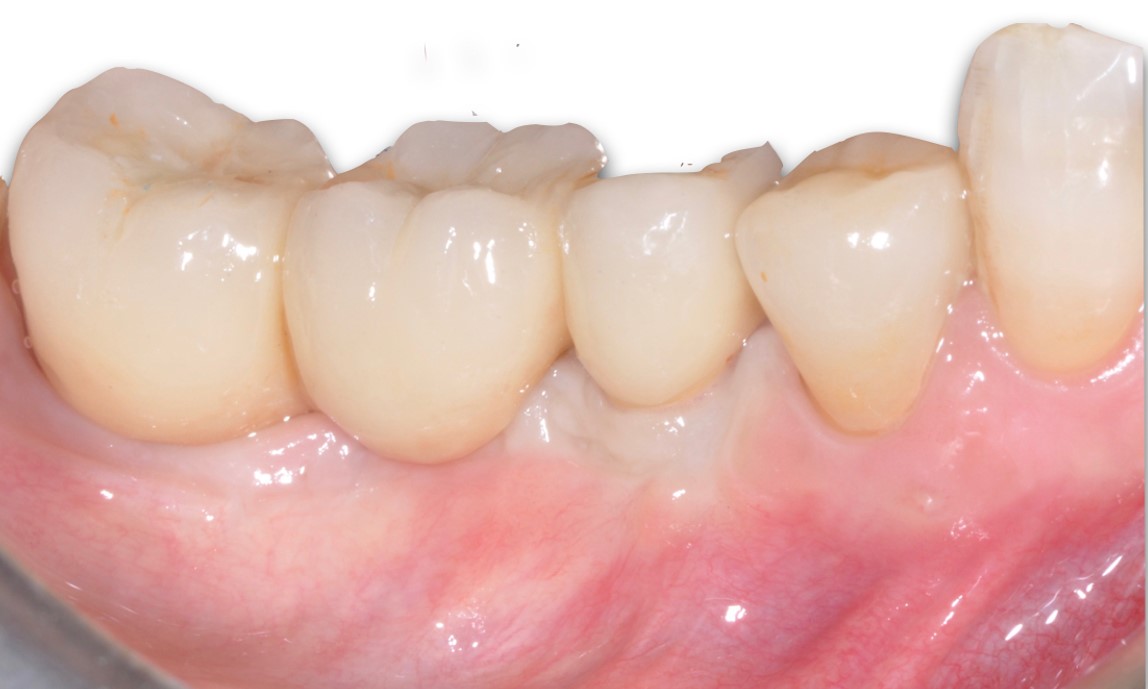

8/9 - Placement of a standard metal-ceramic bridgePeri-implant soft tissue augmentation for pontic with mucoderm® - Dr. M. Frosecchi